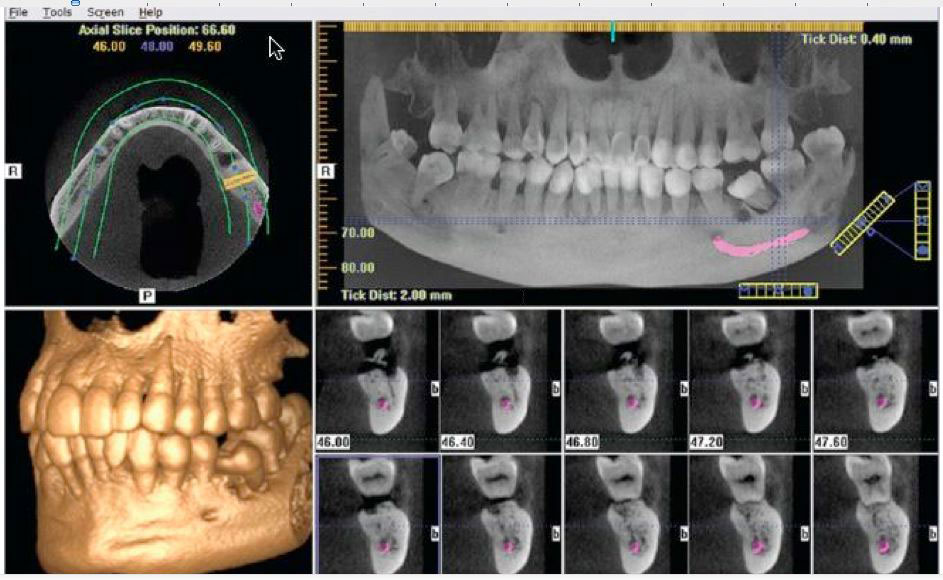

Today’s advanced surgical techniques require precise and informative planning to assure both the surgeon and the patient that as many variables as possible have been considered and analyzed before surgical procedures are commenced. We use a Gendex 500 HD Cone Beam CT Scanner in our office to provide our surgeons with incredibly accurate cross-sectional and 3-dimensional images of our patient’s surgical anatomy. These digital images digitally replicate mouth and jaw anatomy, providing our doctors with critical information concerning precise tooth positions, bone structure, locations of relative anatomy and vital structures using complete 360 degree, three-dimensional scans. Not only can they view the exact nature of your bony anatomy, but they can also use these images in a digitized virtual reality model to evaluate various treatment options that could be utilized in your particular case.